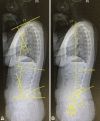

Results: In terms of QoL, psychological assessment and a detailed history, bodily pain in SF-36, SRQ-D, and family stress were significantly associated with NSP. A VAS of pain and numbness to the arm, and from thoracic region to legs, was significantly associated with NSP. There were no statistical correlations between the VAS and radiographic parameters of the cervical spine. Among the whole spine sagittal measurements, multiple logistic regression analysis showed that sacral slope (SS) and sagittal vertical axis (SVA) were significantly associated with NSP.

Conclusion: In this study, we showed the factors associated with NSP. Large SS and reduced SVA were significantly associated with NSP, while cervical spine measurements were not.